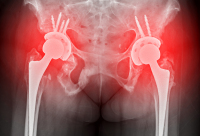

髋骨骨折患者问:髋骨骨折的治疗方式有哪些?

大家好,我是一位深受髋骨骨折困扰的患者,近期一直在寻找合适的治疗方式。在这里,我想分享一下我的经历,并就治疗方式的问题向医生提问。在我遭受骨折之前,我一直觉得养狗是一种非常幸福的事情。这只大狗陪伴我度过了许多寂寞的日子,它对我的忠诚和依赖让我感到非常的安慰。但是,当我去出差归来,迎接我的却是一场意想不到的灾难。那只大狗见到我后的激动扑抱,直接导致我整个人摔倒在地,结果检查出髋骨折了。医生告诉我,髋骨骨折的治疗方式主要取决于骨折的严重程度和患者的身体状况。这让我感到有些困惑,因为我并不想长期卧床休息或接受手术。然而,医生解释说,如果骨折部位没有发生移位,可以采用保守治疗。这包括卧床休息、下肢皮肤牵引或骨牵引等方式来保持骨折部位稳定。如果疼痛剧烈,还可以遵医嘱服用药物进行治疗。然而,如果骨折严重,如开放性骨折或关节不稳定、有错位或畸形等问题,就需要及时进行手术治疗了。手术方法可能包括切开复位术,即将股骨头在髋臼内得到同心圆坐落,以恢复正常功能;或者是髋关节置换术,用于缓解关节疼痛、矫正畸形、恢复和改善关节的运动功能。在这里,我想问问大家,对于像我这样的患者来说,哪种治疗方式更为合适呢?保守治疗是否适用于所有类型的髋骨骨折?手术治疗又是否是最佳选择?希望医生们能给出一些建议和意见。总之,我希望我的经历能够给其他有类似问题的患者一些启示和帮助。无论你选择哪种方式进行治疗,都要相信医生的专业意见,积极配合康复训练,相信我们都能早日康复。